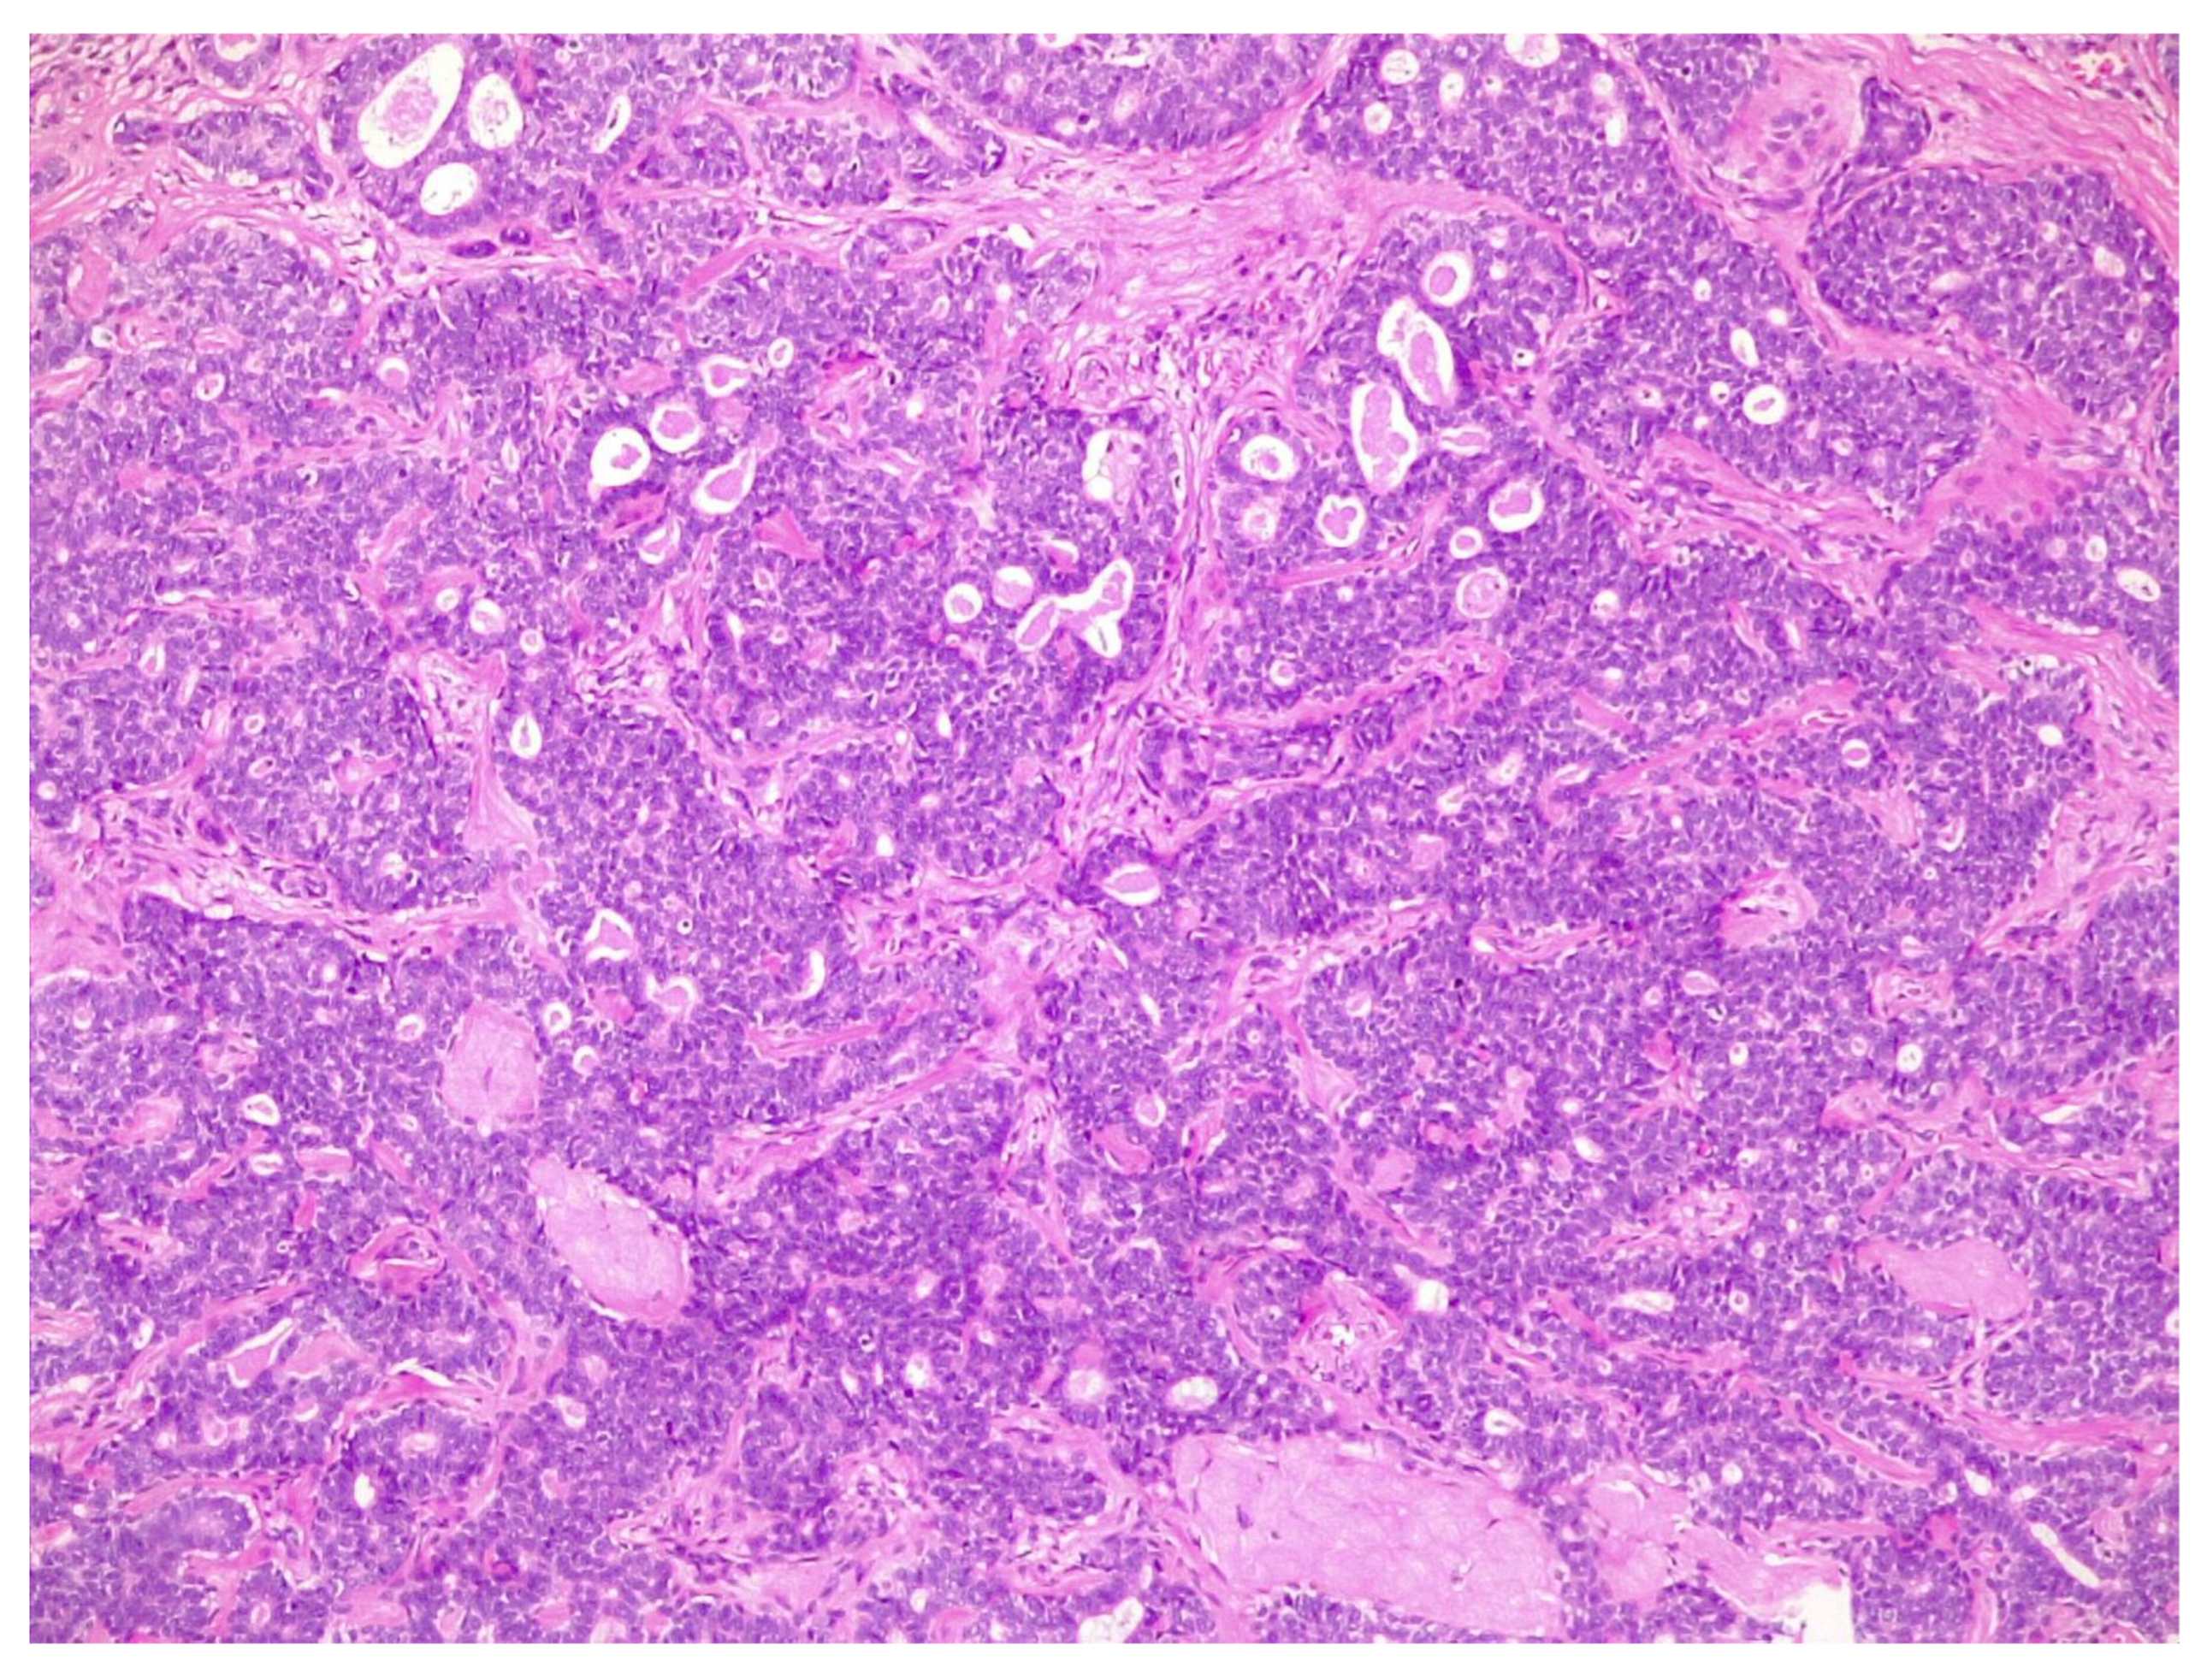

2.2. Figures